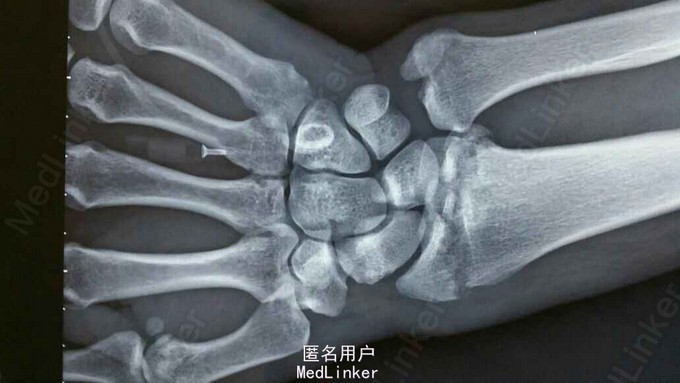

患者于2015年8月18日从高处坠落(约7米)伤及双碗,肿胀,畸形,活动受限。

双碗畸形明显,肿胀明显,可见明显皮下淤血,压痛阳性,可触及明显骨察感及骨察感,左手有明显正中神经压迫症状。

诊断:双尺桡骨远端粉碎性骨折 治疗:入院后,给予手法复位夹板固定,左手神经症状明显缓解,给予对症治疗,消肿后,于2015年8月27日行手术治疗。